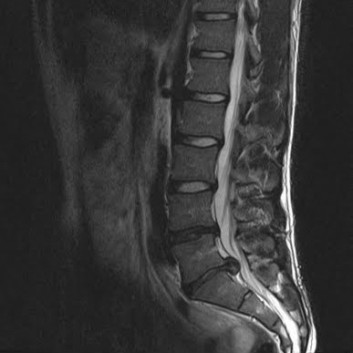

급성 디스크 손상 및 디스크 탈출증

허리 디스크에 의한 급성 통증 발생 시에도 심부신경 주사치료를 통해 효과적으로 통증을 조절 할 수 있습니다. 갑작스런 자극에 의한 신경의 통각 과민을 예방하고 붓고 파열 된 디스크의 크기를 줄임으로써 수술 없이 안전하게 치료가 가능합니다. 효과적인 치료를 위해 반복해서 치료 해야 합니다. 심각한 디스크의 파열은 수술이 필요 할 수도 있습니다.